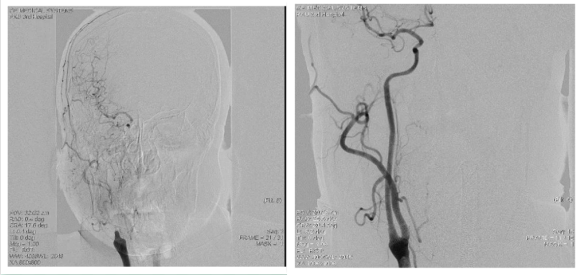

心脏中心成功为96岁高龄老人完成经心尖主动脉瓣置换术

1924年出生的李爷爷(化名)是我国著名的地质学家,退休后也一直在为我国的地球化学事业作贡献。仅在两年前,年近百岁的李爷爷身子骨还很硬朗,耳聪目明。但这两年的健康状况却急转直下,夜里睡觉总是间断地喘憋,白...